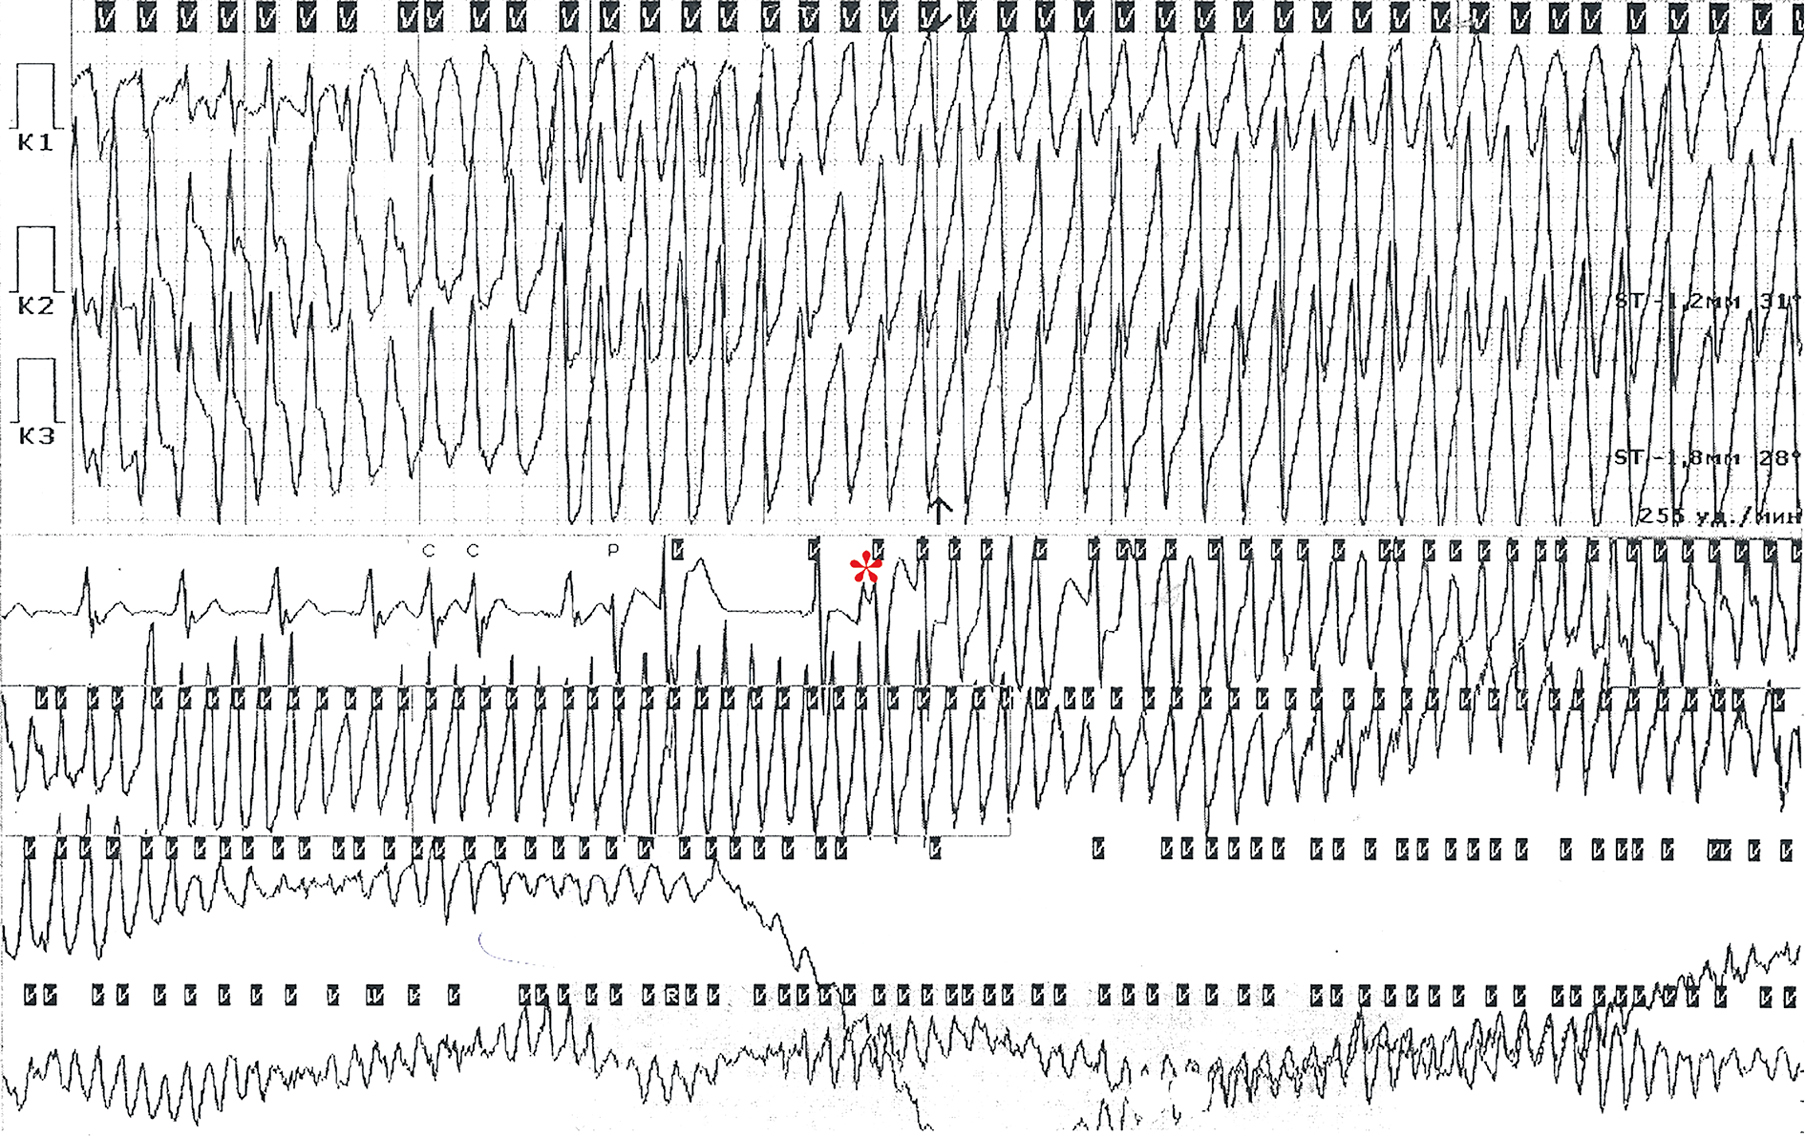

In patient 642c (male, 15 years old), the disease manifested at age 15 years with the development of cardiac arrest caused by polymorphic VT/VF (Fig. 5). CPR was performed, and a ICD was implanted for secondary prevention of SCD. Genotyping revealed a pathogenic mutation, c.14876G > A (p.Arg4959Gln, rs794728811), in the RYR2 gene. Based on these results, CPVT was diagnosed. The mother of the proband was found to have the same mutation, which manifested clinically as presyncope and palpitations.

Fig. 5. 24-hour Holter ECG of patient 642с. Ventricular premature beat, R on T pattern (red asterisk), initiated a paroxysm of ventricular tachycardia with transformation into ventricular fibrillation